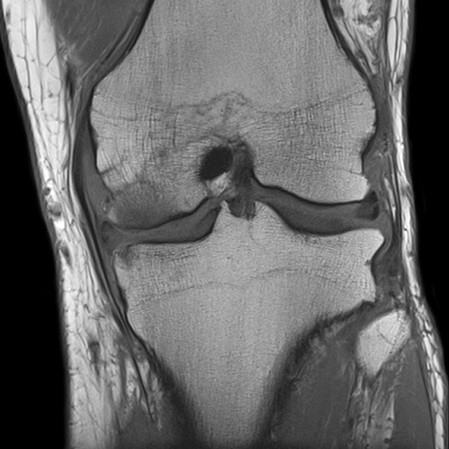

Khớp gối: Nhiều chuỗi xung 3D cho độ phân giải rất cao, hiển thị sụn viền rõ cùng nhiều chương trình giúp đánh giá thoái khớp khớp sớm

Hình 16. Hình ảnh MRI khớp gối